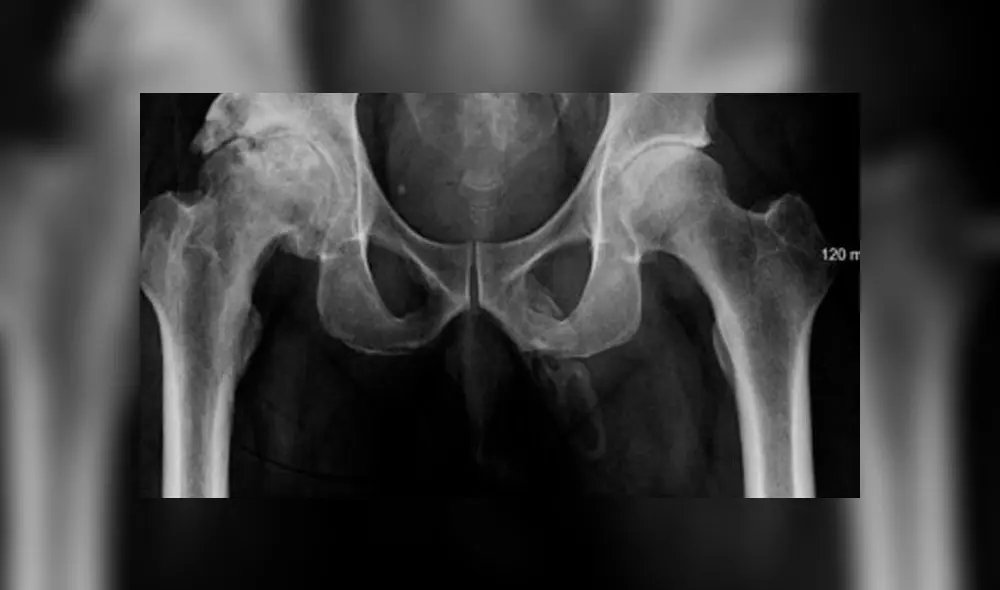

Frente al especialista, el sujeto refirió que además de un dolor en la rodilla, había estado sintiendo ciertas dolencias en el pene. El procedimiento que escogió el médico fue una revisión a la próstata y una radiografía a la pelvis del paciente para conocer si había algún tipo de fractura.

Lo que determinaron los resultados de los análisis sorprendieron a todos pues se halló que el sujeto tenía una acumulación de calcio anómala en los tejidos blandos del pene. Es decir, su miembro estaba recubierto de hueso.

El diagnóstico fue uno: osificación del pene, extraña enfermedad que hasta la fecha se ha registrado solo en 40 informes médicos.

El origen de este padecimiento que consiste en una acumulación de sales de calcio en el miembro viril varía de acuerdo al paciente. En el caso de este hombre no se pudo detectar la causa real de la aparición de la osificación pues este decidió retirarse del nosocomio pese a los consejos de los médicos.

Una investigación registrada en Urology Case Reports señaló que el tratamiento para esta extraña enfermedad dependerá del origen, extensión y sensación de dolor que sienta el paciente por lo cual se pueden establecer observaciones periódicas, uso de analgésicos orales, inyecciones intralesionales hasta estiramientos mecánicos y terapias de ondas de choque extracorpóreas. El informe señaló a la intervención quirúrgica como la última opción.